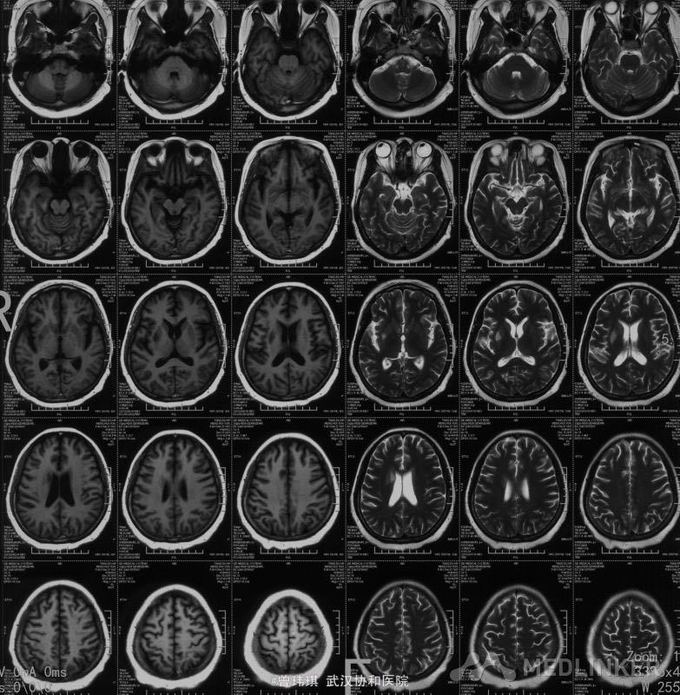

入院查体:四肢肌肉、胸骨、椎骨、膝关节压痛。双上肢肌力Ⅳ级、左下肢肌力Ⅱ级、右下肢肌力Ⅲ级;胸2平面以下痛觉减退,双侧肱二头肌、肱三头肌腱反射(++)、膝腱及跟腱反射(+-++)、左侧霍夫曼征阳性、双侧巴彬斯基征阳性。 骨髓穿刺(第一次):骨髓增生稍低,出现浆细胞卫星现象,并有瘤样改变,嗜血细胞增多,骨髓小粒中造血细胞增多。 复查骨髓穿刺(第二次):增生细胞稍低,浆细胞有瘤样改变,网状细胞、异常吞噬细胞明显。 再次复查骨髓(第三次):增生性骨髓,巨核细胞数正常,血小板减少,粒红可见轻度病态造血现象,浆细胞、网状细胞易见。 外院:血清Kappa轻链4.95g/L;免疫球蛋白G1870mg/L(723-1685),免疫球蛋白A 410mg/dl(69-382),免疫球蛋白M 31mg/dl(63-277),KAP 545mg/ml(170-370),LAM 273mg/dl。 肿瘤标志物:NSE 53.88ng/ml,铁蛋白 2476ng/ml。 自身抗体谱、血T-SPOT、G试验、GM试验、肝炎系列、梅毒、艾滋抗体等均未见异常。 PET提示右侧下鼻甲葡萄糖代谢增高,骨髓及脾脏大、葡萄糖代谢增高。 头颅MRI+颈椎+胸椎MRI扫描:1、右侧侧脑室、豆状核及外囊异常信号影,考虑脑梗塞,建议DWI检查;2、颈椎间盘突出(颈4-5、5-6,中央型);颈6椎体骨岛;3、胸3-6椎体水平椎管内异常信号影,建议增强扫描。